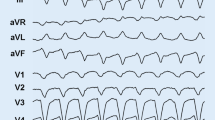

The electrophysiologic substrate of sustained VT in the setting of structural heart disease is usually represented by scar-related reentry, and the destruction of this substrate can potentially prevent VT (Fig. 10.2). The EAM substrate typically involves the basal perivalvular region of the LV and the interventricular septum with a high prevalence of midmyocardial or subepicardial substrates. Two typical scar patterns (anteroseptal and inferolateral) are found in up to 90% of patients with DCM and VT [66, 76]. Two VT morphologies are usually seen in presence of anteroseptal substrate: RBBB with inferior axis and positive concordance throughout the precordial leads or LBBB with inferior axis and early (≤V3) precordial transition (Figs. 10.3 and 10.4) [76]. Occasionally, VT arising from the septum may also present a characteristic precordial transition pattern break in V2 with a predominant R wave in V1 and V3 but an abrupt loss of the R wave in lead V2 due to an exit close to the anterior interventricular sulcus (opposite to lead V2) [66, 77]. A predominant inferolateral substrate can instead be identified in about half of the patients, and, in the majority of them (about 60%), the critical VT sites are located on the epicardium. These patients typically present VTs of RBBB morphology with right superior axis and late (≥V5) precordial transition (Fig. 10.5) [76]. The distinction between these two patterns is of great clinical value in terms of both procedural planning and outcomes. In patients with a predominant anteroseptal substrate, an epicardial approach is largely unnecessary, and the complex local anatomy (i.e., proximity to coronary vessels, presence of epicardial fat) usually limits the possibility to perform CA. Conversely, an epicardial approach is often required to achieve VT control in patients with a predominant inferolateral pattern. Even if epicardial coronary vessels and the phrenic nerve may obstacle epicardial CA in patients with inferolateral substrate, these patients typically have a more favorable outcome (75% vs. 25% VT-free survival at 1.5-year follow-up) and a lower need for redo procedures (7% vs. 59%) compared to patients with anteroseptal substrate [69]. In patients with septal VTs, the intramural location of the substrate can be difficult to address and may require sequential LV and right ventricular (RV) CA as well as the use of high RF energy potentially leading to collateral injury of the conduction system. A series of different approaches like bipolar RF ablation, high-intensity focused ultrasound, retractable needle ablation, and intracoronary ethanol ablation have been described to overcome the aforementioned limits, but none of them is currently available in routine clinical practice.

Example of a 60-year-old lady with idiopathic dilated cardiomyopathy and left ventricular (LV) ejection fraction of 30% presenting with multiple ventricular tachycardias (VT) with both left bundle and right bundle branch morphology and inferior axis (a) consistent with an origin from the interventricular septum. Electroanatomic voltage mapping showed the presence of a small bipolar (b) and a larger unipolar (c) voltage abnormality involving the anterior septum. Extensive septal substrate ablation was performed from both the right and left side of the septum (b–d, red dots) targeting sites showing late potentials (d, red arrow) and long stim to QRS (e)

A variety of criteria can be used to address the need for epicardial mapping/ablation: (1) a 12-lead ECG of the VT suggesting an epicardial origin; (2) evidence of epicardial substrate on imaging studies (i.e., magnetic resonance, intracardiac echocardiography); (3) a unipolar voltage abnormality (<8.3 mV) in the presence of no or minimal bipolar (<1.5 mV) abnormality; and finally, failure of endocardial ablation (either early VT recurrence or persistent inducibility of clinical VT). Epicardial ablation approach is usually associated with a higher incidence of complications; moreover, in a substantial proportion of cases (about 30%), even if critical VT sites are found on the epicardial surface, CA cannot be safely performed due to close proximity of epicardial coronary vessels and left phrenic nerve or presence of epicardial fat. Several ECG features have been correlated to epicardial VT origin like wide QRS complexes (shortest RS complex in precordial leads ≥121 ms), slow initial upstroke of the QRS complex “pseudo delta wave” ≥34 ms, intrinsicoid deflection time ≥85 ms, and maximum deflection index (shortest QRS onset to maximum precordial deflection/QRS duration) ≥0.55 (Fig. 10.6) [78].

Example of a 50-year-old man with mildly dilated cardiomyopathy and left ventricular (LV) ejection fraction of 40% presenting with recurrent ventricular tachycardia (VT) despite antiarrhythmic drug therapy with amiodarone and mexiletine. Baseline 12-lead ECG (a) shows a VT with right bundle branch block morphology and left superior axis consistent with an origin from the inferolateral LV. The clinical VT was easily inducible at the beginning of the procedure with programmed ventricular stimulation (b) and was still inducible after extensive endocardial LV ablation (c–d, red dots) performed at sites showing local abnormal ventricular activity (LAVA) (c–d, black dots). Epicardial mapping (e) demonstrated a large voltage abnormality involving the basal lateral LV wall with presence of LAVA (black dots). A good pace mapping site was identified in the inferolateral mid-wall (f). Mid-diastolic activity was recorded at this during VT (g, red arrows). Radiofrequency ablation here resulted in termination of the clinical VT which was no longer inducible